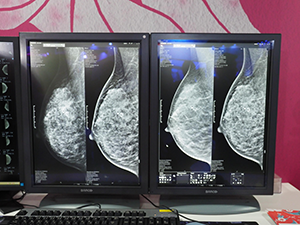

女性医療のコーナーでは,デジタルマンモグラフィ「MAMMOMAT Inspiration」と「MAMMOMAT Fusion」が展示された。精密検査対応機種になるMAMMOMAT Inspirationには,新しいトモシンセシス機能“High Definition Breast Tomosynthesis(HDBT)”が搭載された。HDBTでは,トモシンセシス画像から合成2D画像を作成する“Insight2D”,逐次近似再構成法とFBP法を組み合わせたトモシンセシス画像“EMPIRE”,角度を変えながらトモシンセシス画像を回転表示する“Insight3D”が可能となった。シーメンス独自のInsight3Dでは,画像を回転させながら観察でき,より病変を検出しやすくなっている。既存ユーザーには,バージョンアップで対応する。

マンモグラフィの上位機種MAMMOMAT Inspiration |

新しいトモシンセシス機能HDBT |